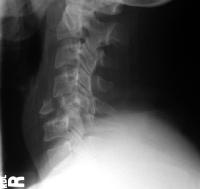

Upper Cervical Spine Injuries

Fractures & dislocations of Cervical Spine

Intervertebral discs & spinal nerves